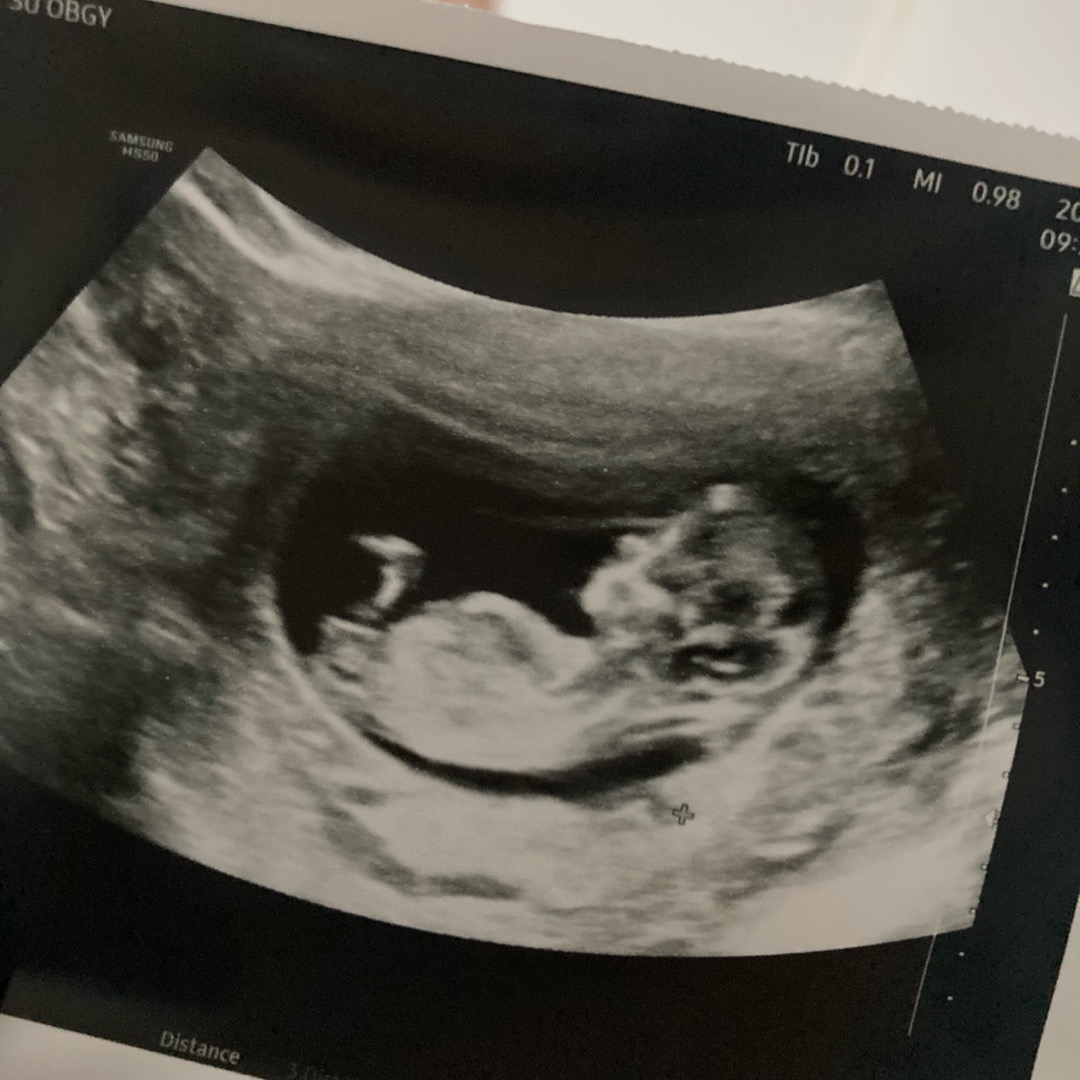

11주차 초음파❤️

임신5주차부터 시작된 입덧지옥으로 11주차 -6키로 찍고 입덧약 처방과 1차 기형아 검사받고 건강한 아기모습이에요 넘 귀요워서 올려요 ...ㅎ

코가 오똑하네요~ 이와중에 각도는 딸각도같고요